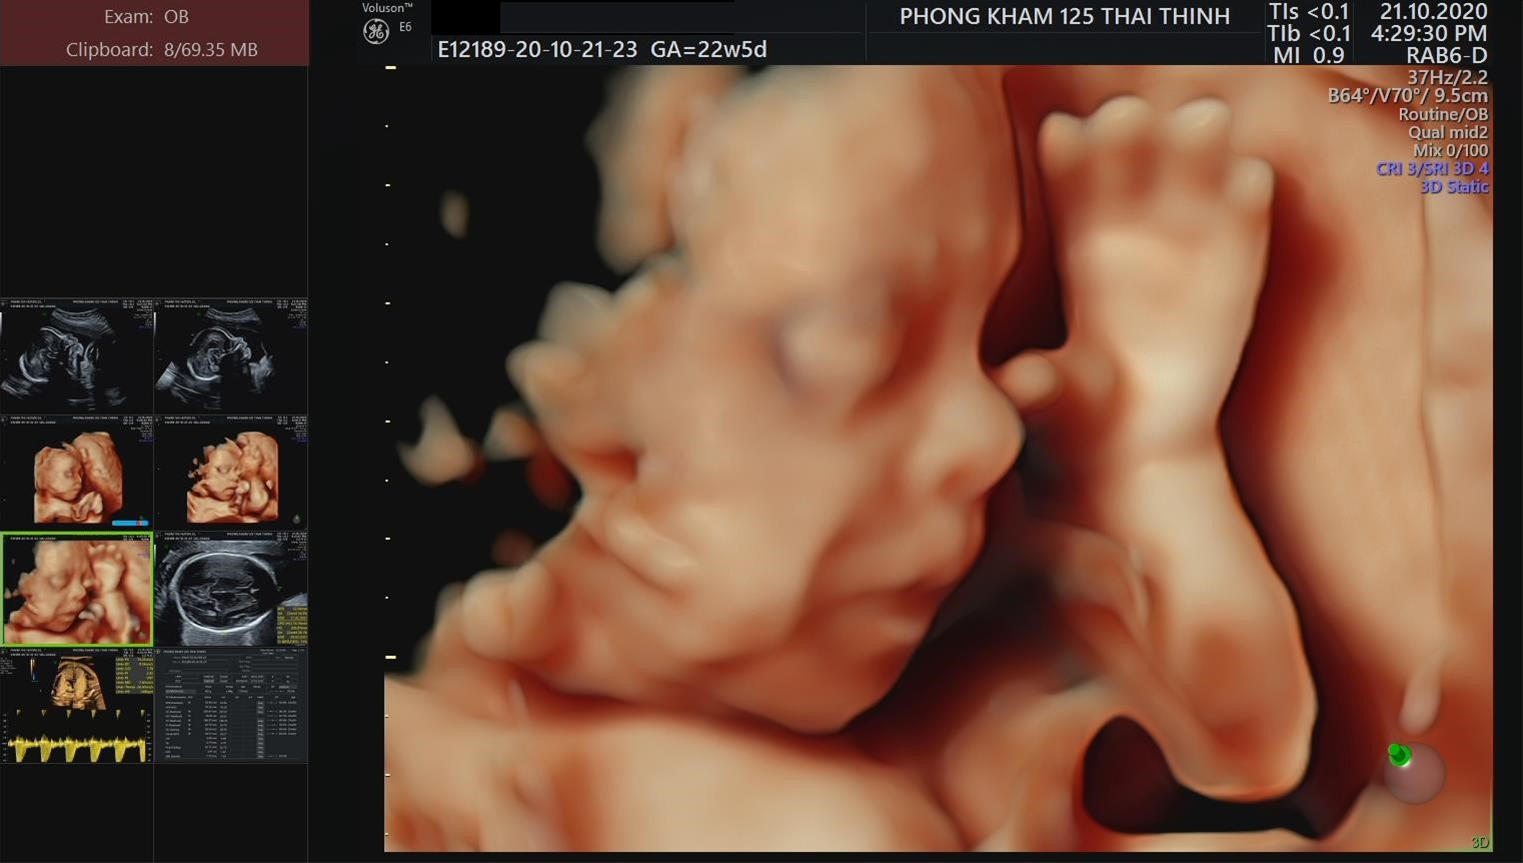

Thời điểm: Nấc có thể xuất hiện bất kỳ lúc nào, không kể ngày đêm. Bà bầu có thể nhìn thấy hình ảnh con nấc qua siêu âm thai nhi.